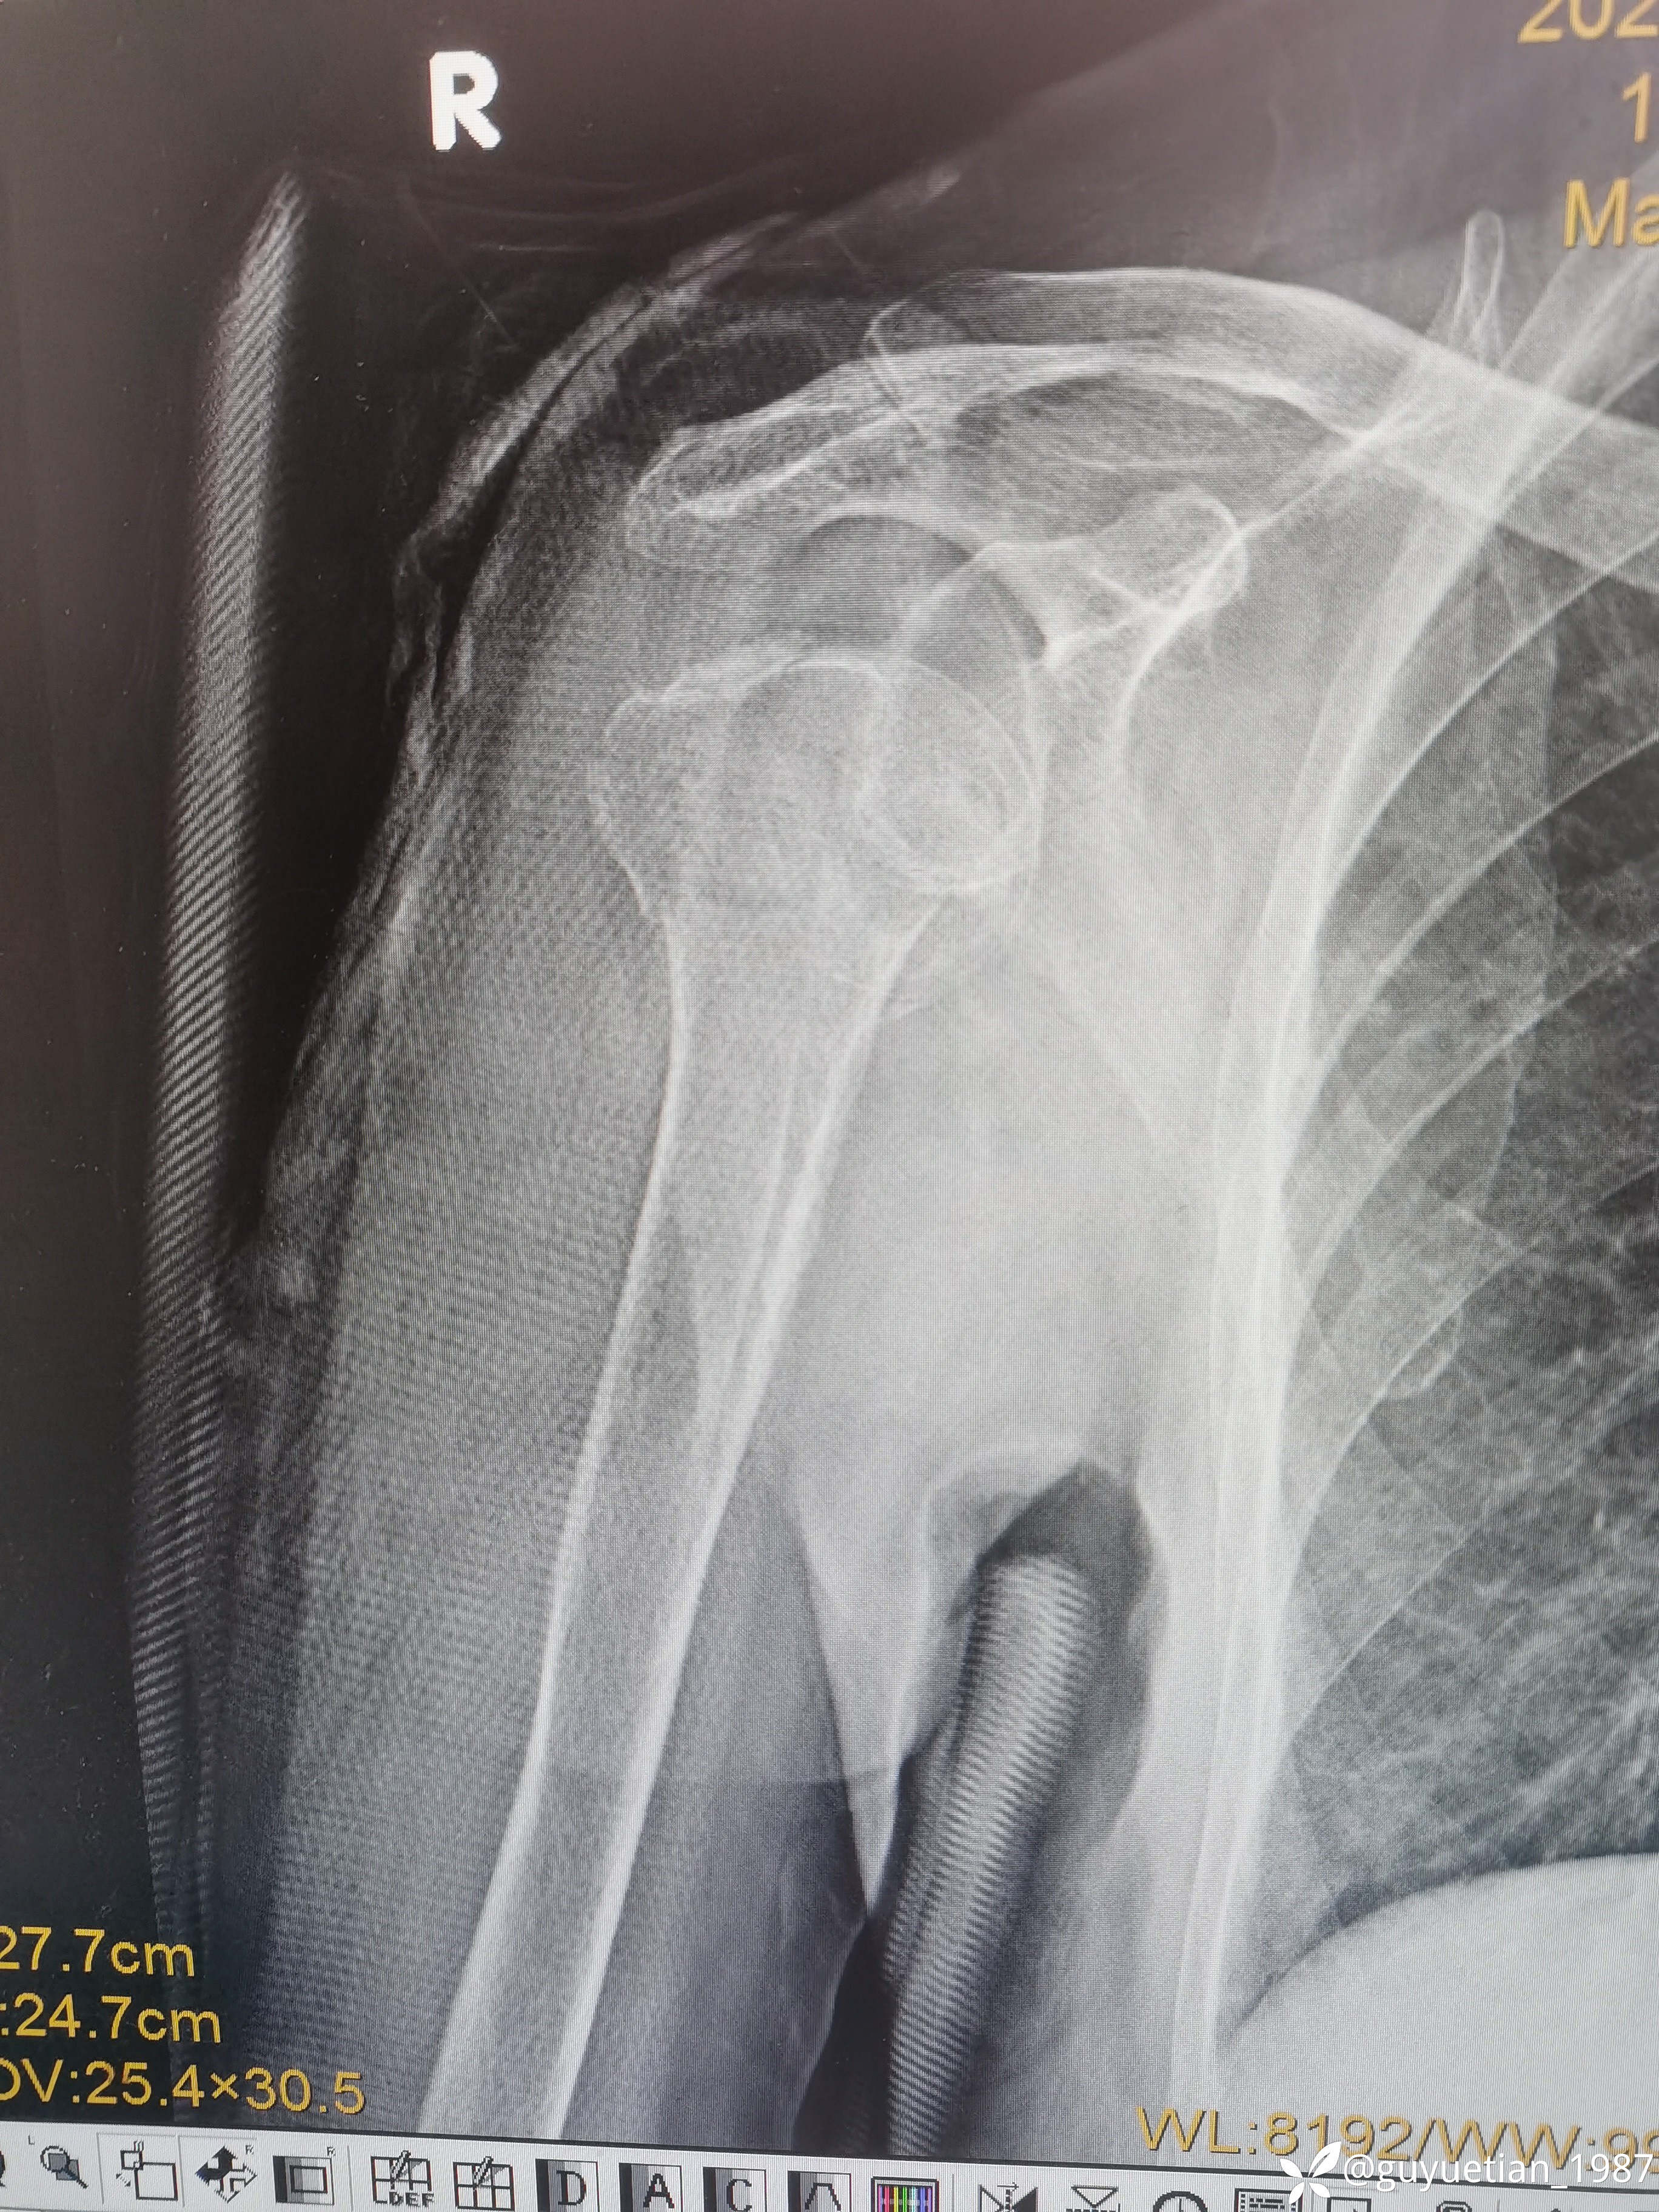

家属沟通后倾向于保守,那就尽力而为

可以接受,夹板固定,嘱耸肩、握拳锻炼。